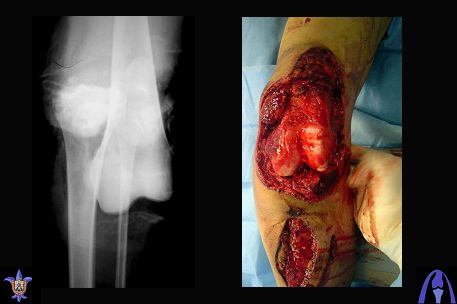

Re: open dislocation of the knee joint

Снимки прошлых публикации из моего Power point